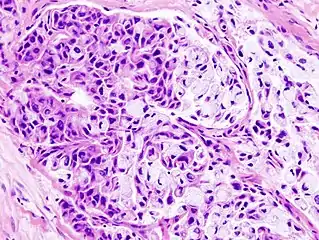

Histopathologic image of mucoepidermoid carcinoma of the major salivary gland. H & E stain

Histopathologic image of mucoepidermoid carcinoma of the major salivary gland. The same lesion as shown in a filename "Mucoepidermoid carcinoma (2) HE stain.jpg". H & E stain

In terms of diagnosis we find that histological staining, radiological imaging and molecular diagnostic features all play a role in the evaluation[1] This tumor is not encapsulated and is characterized by squamous cells, mucus-secreting cells, and intermediate cells.[7]